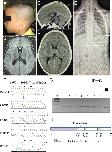

Fig 1. KIF6 mutation in a child with intellectual disability.(A) A low-set prominent anti-helical left pinna. (B) MRI of the brain at 7 months-old shows dolichocephaly with a normal brain structure. (C) and (D) CT of the brain at 8 years-old, sagittal and axial views, respectively show dolichocephalic shape of the cranium (cephalic index = 75) without demonstrable intracranial abnormality. (E) X-ray of the spine shows no scoliosis (F) Electropherograms of the patient, a control, the patient’s father, mother, and unaffected brother from top to bottom. The patient is homozygous for the c.1193delT mutantion while his father, mother, and unaffected brother are all heterozygous carriers. (G) Pedigree and RFLP, using MfeI restriction enzyme: Lane M = 100 bp marker. The arrow head indicates the 500 bp band. Lanes 1–5 are controls. Lanes 6 and 7 are the proband’s father and mother, respectively, showing that they are heterozygous. Lane 8 is the proband showing that he is homozygous for the c.1193delT. (H) Representative KIF6 structure. The arrow shows the position of the c.1193delT mutation.